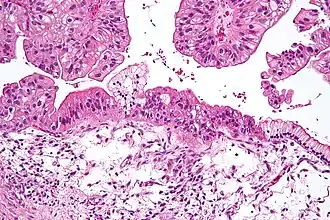

Riscul de cancer ovarian este mai ridicat la persoanele ce ovulează mai multe zile. Astfel, acele persoane ce nu au născut prezintă un risc mai mare, la fel și acele persoane cărora le începe ovulația la o vârstă mai fragedă sau intră la menopauză la o vârstă mai înaintată.[6] Alți factori de risc includ terapia cu hormoni după menopauză, medicamentele pentru fertilitate și obezitatea.[2][7] Factorii ce scad riscul includ contracepția hormonală, ligatura trompelor și alăptarea.[7] Aproximativ 10% dintre cazuri sunt legate de riscul genetic moștenit, iar cei cu mutația genei BRCA1 sau BRCA2 au aproximativ 50% șanse să dezvolte boala. Cel mai comun tip de cancer ovarian, însumând mai mult de 95% dintre cancere, este carcinomul ovarian. Există cinci subtipuri de carcinom ovarian, dintre care cel seros de grad înalt este cel mai des întâlnit. Se crede că aceste tumori pornesc din celulele ce acoperă ovarele,[6] deși unele s-ar putea forma din tuburile falopiene.[8] Tipurile mai puțin comune sunt tumorile cu celule germinale și tumorile derivate din stroma gonadală specializată.[6] Diagnosticul este confirmat prin examinarea unei biopsii prelevate, de obicei, în timpul intervenției chirurgicale.[4]